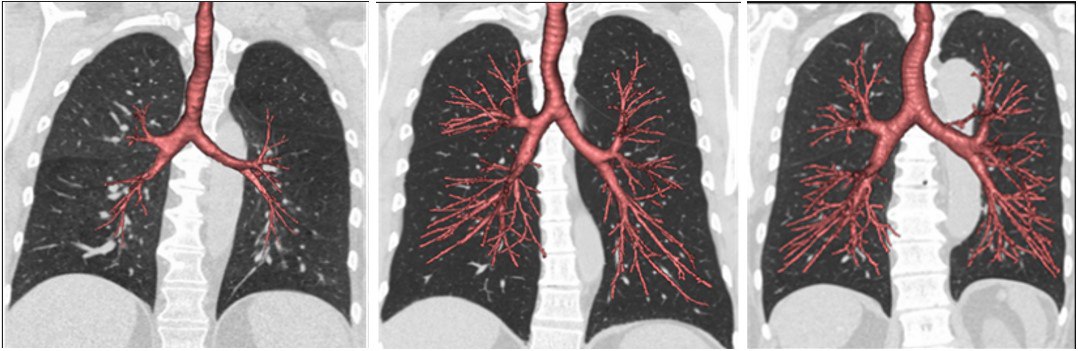

Since the beginning of the year 1980 and at the beginning of the first days of the Iran-Iraq war, which lasted 8 years, and because of the lack of resources and the many sad situations that began to appear clearly on the Iraqi people, and after entering Iraq into a war with the neighboring country Kuwait, it fell ill in 1990 and Iraq invaded it and the occurrence of the popular uprising in 1991 and the siege began on Iraq by the United Nations, and since then, there have been clear signs of Iraqis going to smoke, clearly and extensively, as an alternative and to alleviate the pain and suffering experienced by these people. Therefore, one of the most important and violent diseases caused by smoking appeared in Iraq..which is COPD<br /><br />COPD is a common disease that mainly affects middle-aged or elderly smokers. many people don't know they have it<br /><br />1. Introduction<br /> Since the beginning of the year 1980 and at the beginning of the first days of the Iran-Iraq war, which lasted 8 years, and because of the lack of resources and the many sad situations that began to appear clearly on the Iraqi people, and after entering Iraq into a war with the neighboring country Kuwait, it fell ill in 1990 and Iraq invaded it and the occurrence of the popular uprising in 1991 and the siege began on Iraq by the United Nations, and since then, there have been clear signs of Iraqis going to smoke, clearly and extensively, as an alternative and to alleviate the pain and suffering experienced by these people. Therefore, one of the most important and violent diseases caused by smoking appeared in Iraq..which is COPD<br />It is estimated that Iraqis consume daily cigarettes worth $1.8 million, the bulk of which goes to importing cigarettes through smuggling from Iraq’s neighboring countries, at a time when the percentage of smokers in the country is estimated at 35% of both sexes, which means that the total number of smokers is About 14 million Iraqis out of a total of 42 million.<br /> 2. patient and methods<br />Smoking in Iraq is a widespread and culturally acceptable behavior in Iraqi society. Since 2003, there has been a lot of pressure from the government to enforce strict smoking rules. In 2009 it became illegal to smoke in or around public buildings, although the ban remains unpopular with the Iraqi public and its enforcement is patchy.<br /><br />A 2015 study by health advocates stated that about 55 Iraqis die every day from tobacco-related illnesses. Compared to 10 people dying daily in Iraq due to terrorism and violence..<br />Smoking in Iraq is a widespread and culturally acceptable behavior in Iraqi society. Since 2003, there has been a lot of pressure from the government to enforce strict smoking rules. In 2009 it became illegal to smoke in or around public buildings, although the ban remains unpopular with the Iraqi public and its enforcement is patchy.<br /><br />A 2015 study by health advocates stated that about 55 Iraqis die every day from tobacco-related illnesses. Compared to 10 people dying daily in Iraq due to terrorism and violence.<br />Tobacco advertising is in theory prohibited, and it is illegal to smoke in public, but these laws are not systematically enforced. A 2015 survey by the World Health Organization found that there were multiple billboards throughout the capital Baghdad promoting tobacco as well as in hospitals and schools. The same survey found that 13% of Iraqi districts do not have smoking cessation programs aimed at helping smokers quit.<br /><br />Government taxes on cigarettes are high but relatively low at less than 50%; Most packages sell for less than a dollar<br />3. Results <br />In many cases that suffer from COPD we found that the progression of the disease leads to a complete collapse of the respiratory system, which necessitates a full intervention and the admission of the patient to the intensive care ward because of the patient's need for artificial respiration, and for this we had to train the workers intensively on how to Dealing with such patients also training staff in the intensive care department who are graduates of anesthesia and intensive care techniques on how to secure the airway and blood supply and how to ensure the complete function-ing of the respiratory system<br />4-discussion<br /> The results of the article include that in the future we must open several halls and specialized centers for the treat-ment of patients COPD especially the opening of special centers in intensive care in all hospitals and from all levels first, secondary and tertiary, and lounges must be provided such as ... because an increase in the number of Iraqi smokers may lead to In the coming days, there will be a significant increase in the number of patients suffering from COPD<br /><br />بواسطة : م. كرار نادر عبد عون